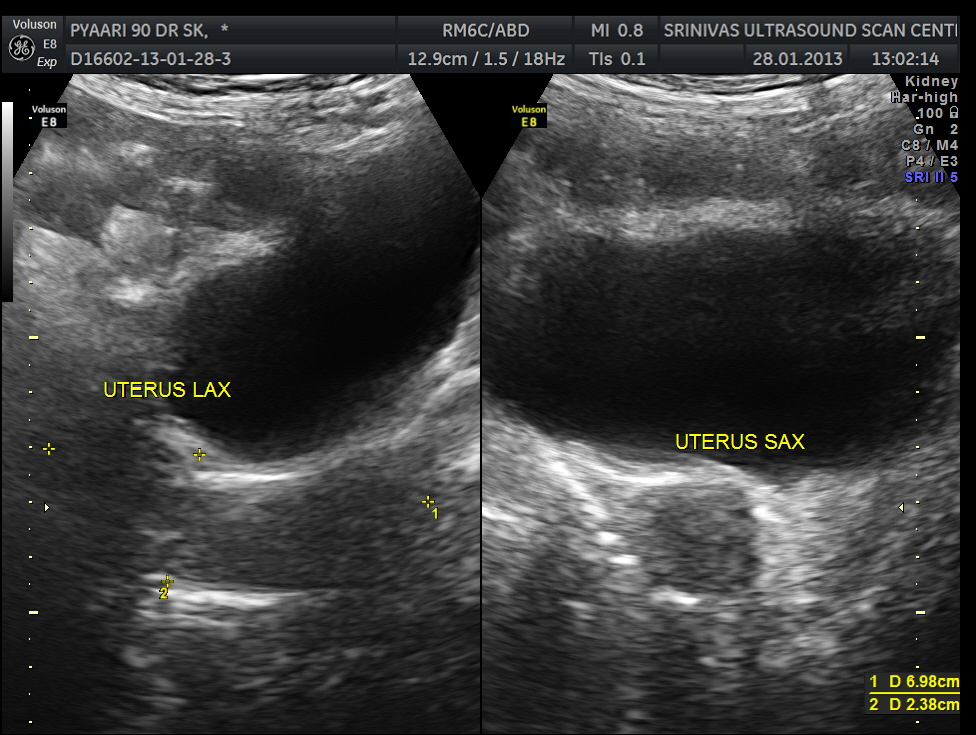

Pelvis appeared to be normal.